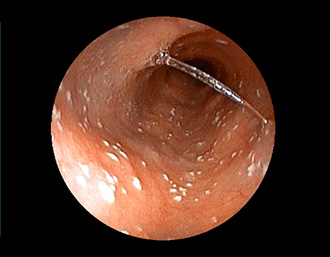

症例1:胃潰瘍(37才、男性)

①胃潰瘍(Stage A1)

健診:胃レントゲン検査で、胃角部ニッシェを指摘され当院受診。

胃角部小弯に、深くて大きな、大きさ約10mmの胃潰瘍(stage 1)

があり、潰瘍底は一部白苔はみ出しを認める。エソメプラゾールマグネシウム水和物投薬で治療開始しました。

(通常画像)